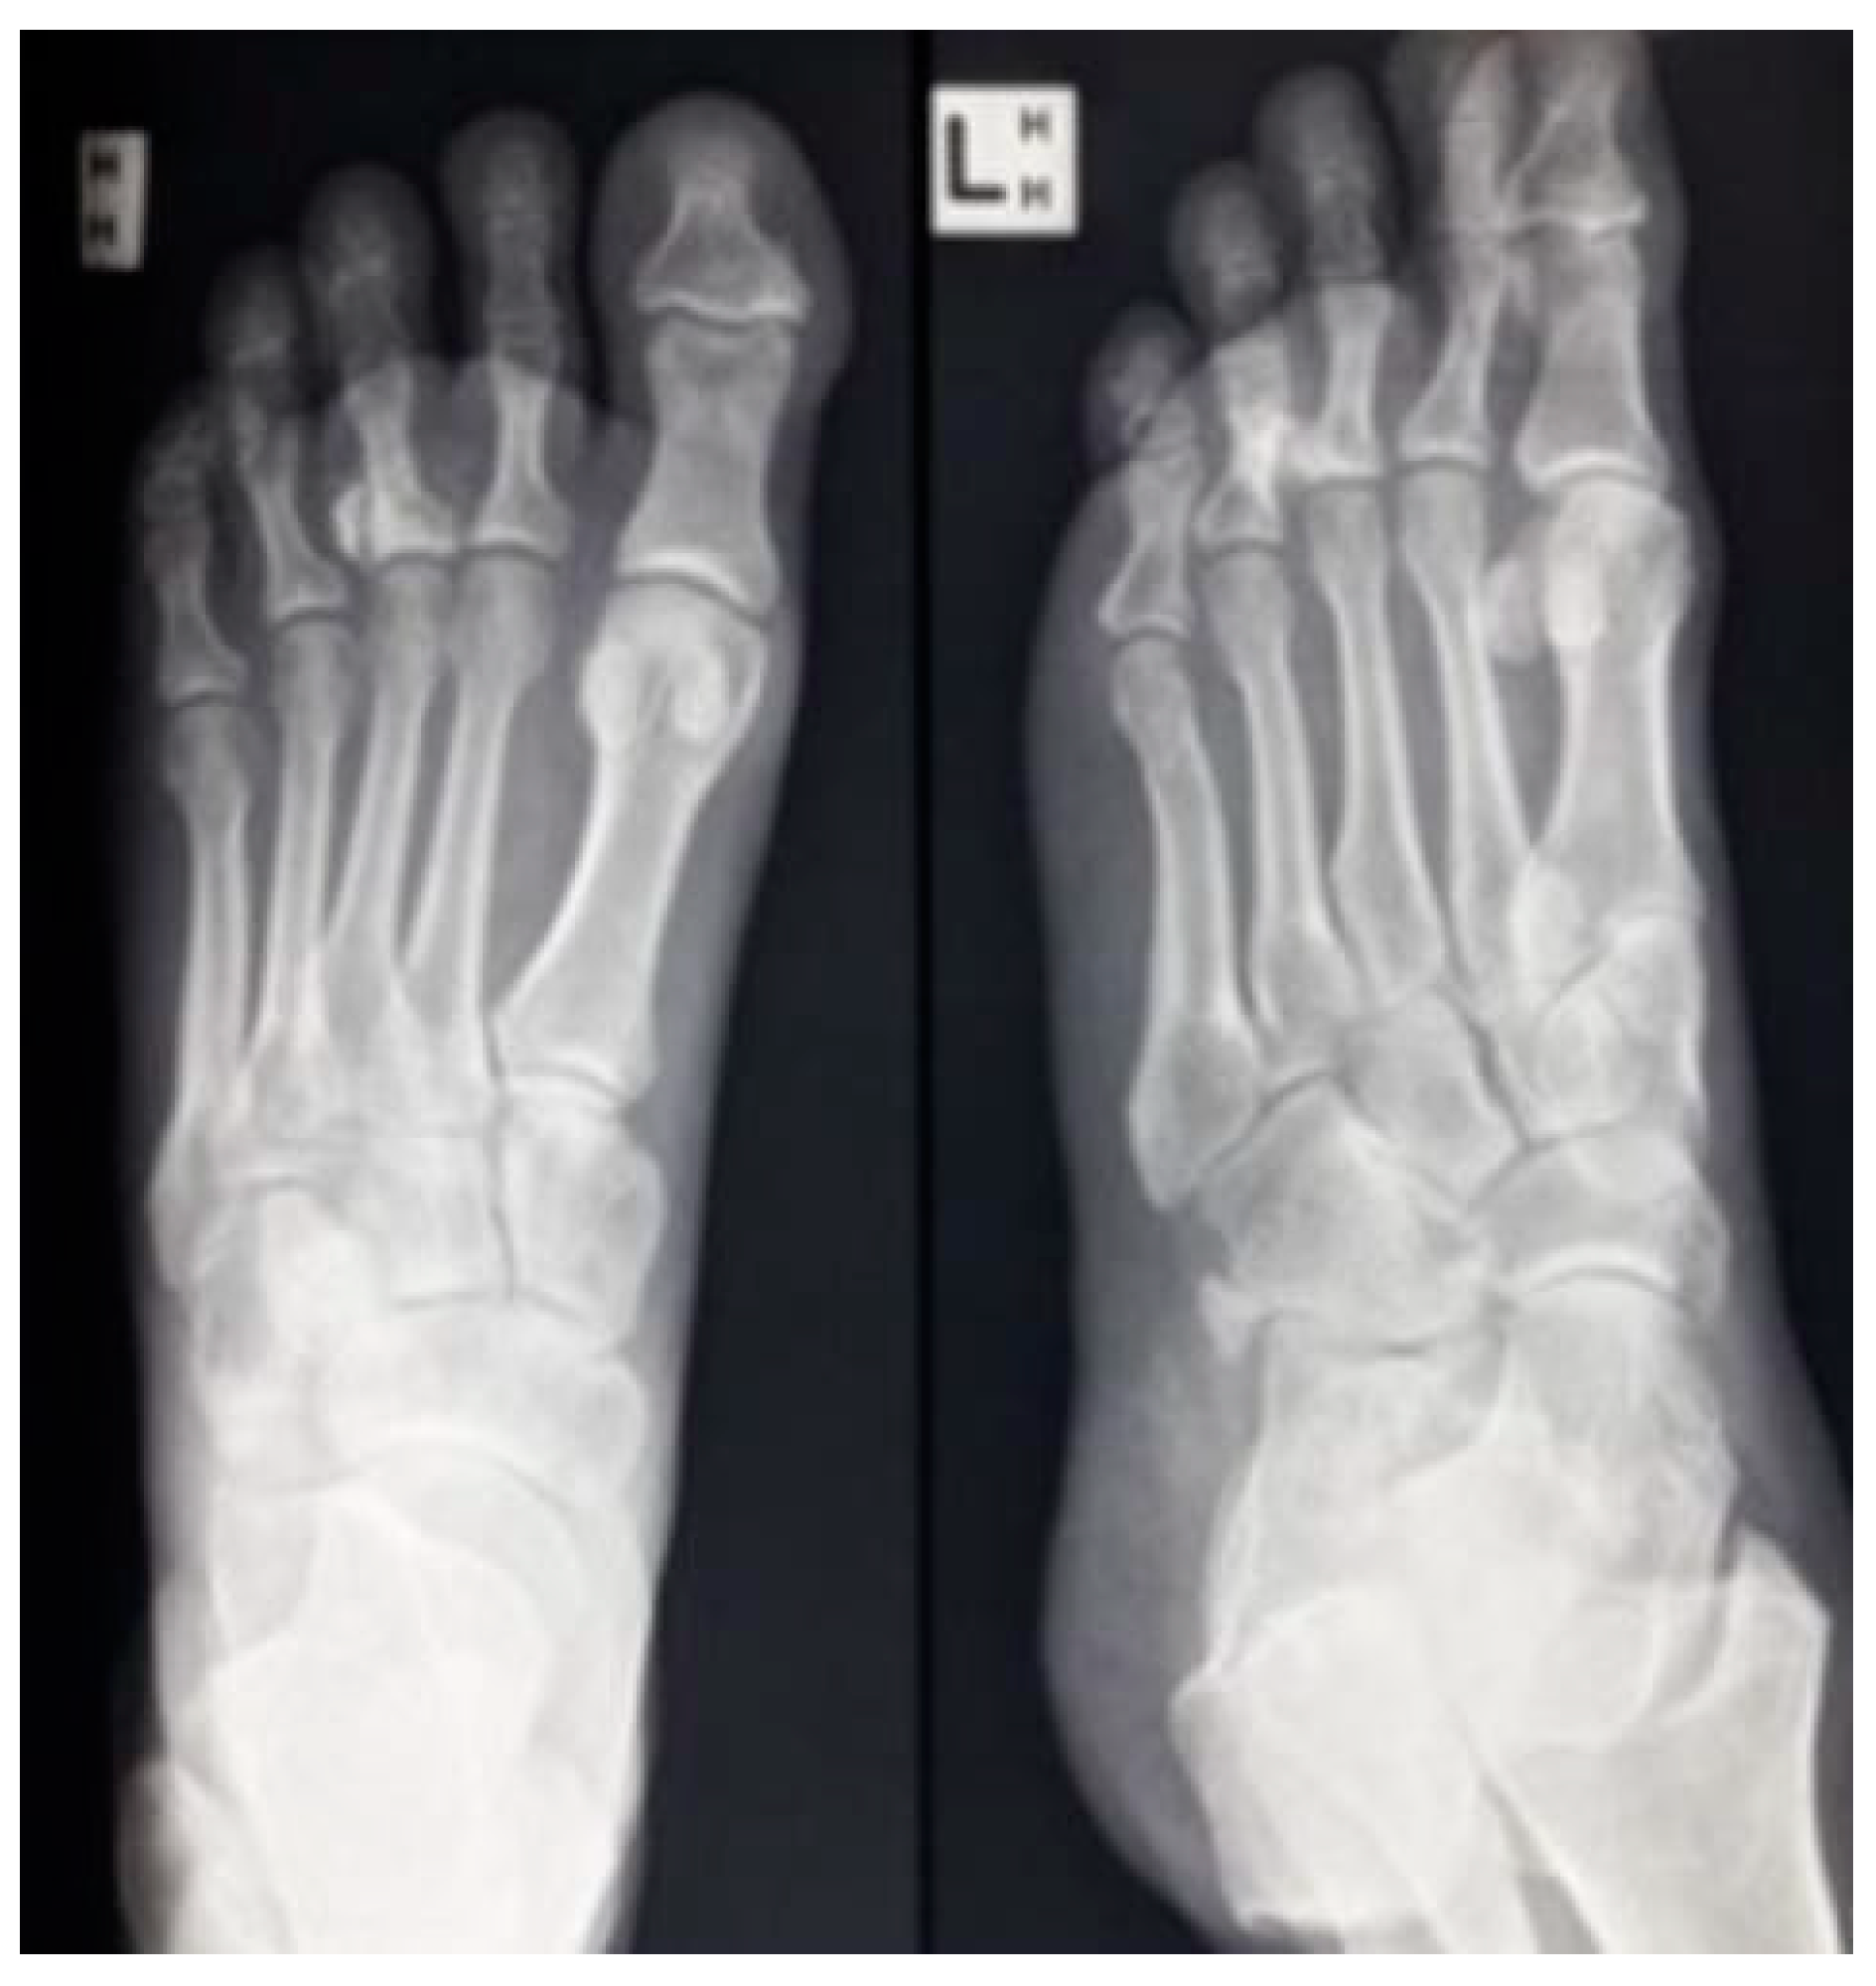

There are various reasons why one might need to use an implant of the metatarso phalangeal joint, including conditions like advanced rheumatoid arthritis, hallux rigidus, and bone infections or amputations that causes joint locking. However, for this study, it’s focalized in the use of the implant of the MTP joint for malignant tumors affecting this part.

Figure 2. X-ray of left foot showing abnormal ossification around 3rd MTP Joint [3].

These tumors can cause significant damage and pain with locking the joint. In such cases, an implant can aid in restoring the lost function and mobility to the impacted area, enabling patients to lead more normal lives and to regain their normal activities. Understanding the use of an implant for malignant bone tumors can help improve the care and outcomes for patients dealing with these conditions.